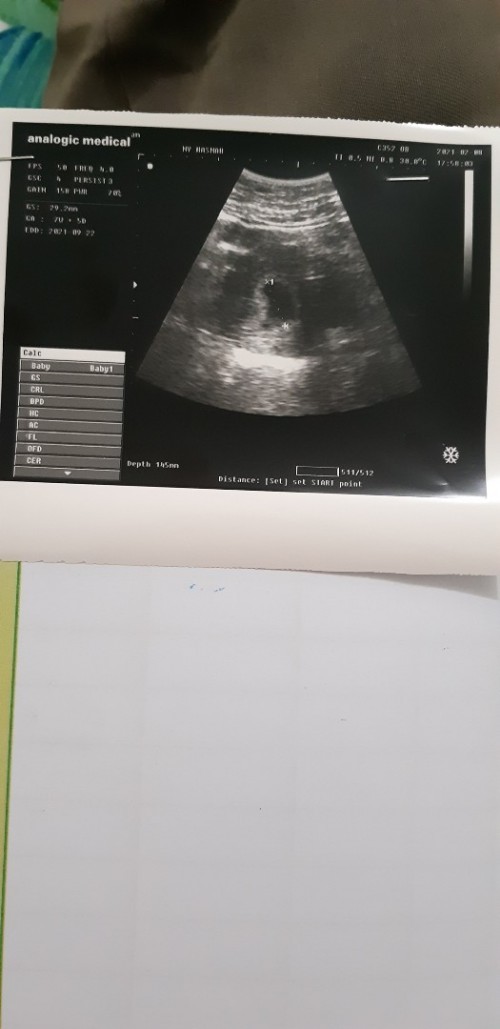

kalo aku CRLnya 0.91 cm GA 6w6d